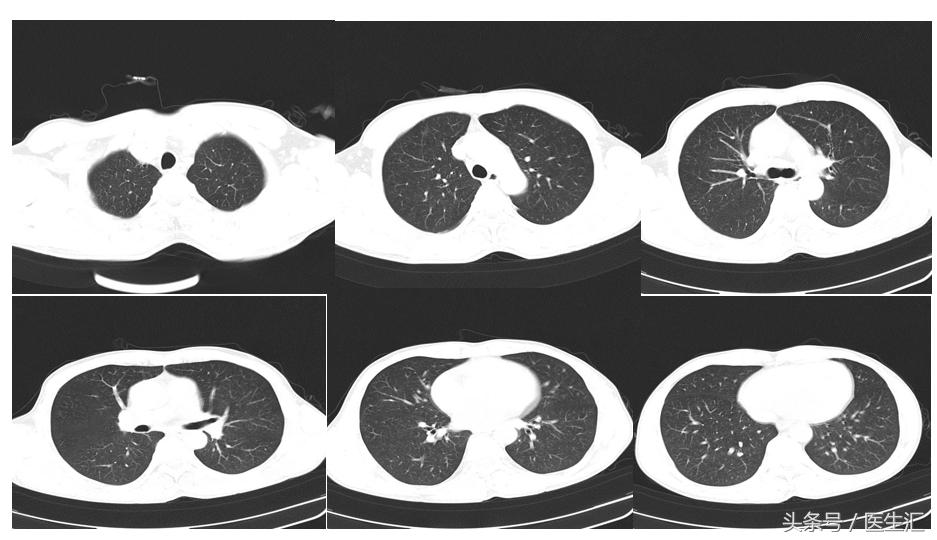

胸部CT

初步诊断:吸入性损伤